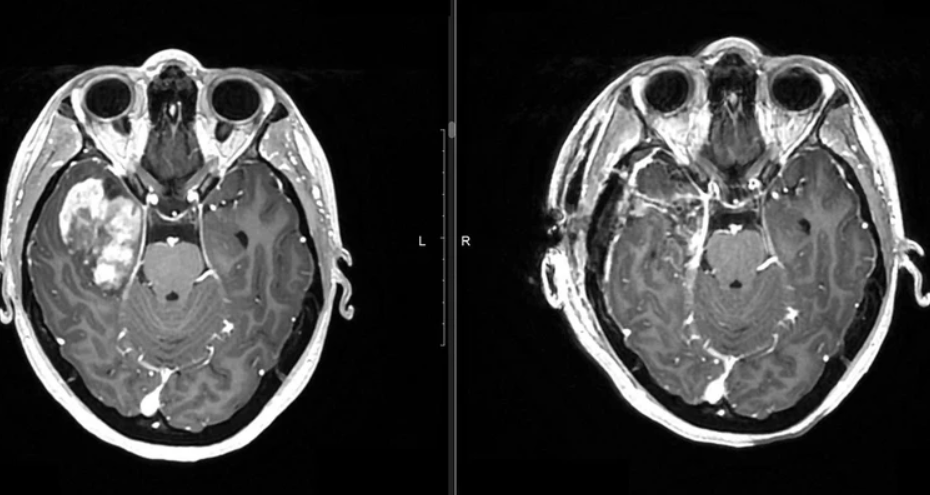

10 января 2025 года сибирячку госпитализировали в нейрохирургическое отделение №1, а 14-го числа провели операцию. Из-за размеров и расположения опухоли – в правой височной доле – было принято решение о проведении открытой операции.

– Это необходимо, чтобы мы могли наиболее точно визуализировать опухоль и удалить её, с учётом того, что границы между пораженными тканями и здоровым мозгом размыты, – объяснил нейрохирург Сергей Мишинов.

Опухоль росла довольно быстро, уже достигла размеров мяча для настольного тенниса. Она продолжала бы увеличиваться, сдавливая здоровые ткани мозга и вызывая серьезные неврологические нарушения, если бы девушке не помогли. Благодаря использованию современных технологий хирургам удалось полностью удалить новообразование.

Фото пресс-службы НИИТО им. Я.Л. Цивьяна